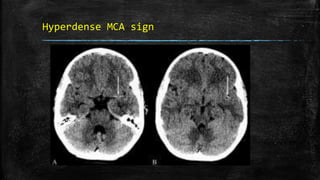

Hyperdense MCA sign

• #76 Hyperdense MCA sign. Noncontrast axial CT scans (A, B) of the brain in a patient with sudden-onset right hemiparesis show hyperattenuation of the left middle cerebral artery (arrows). This is suggestive of occlusion of the artery. This is one of the signs of acute stroke but does not necessarily represent infarction